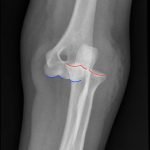

Elbow dislocations are classified by the position of the radio-ulnar joint relative to the humerus.1 Images 1, 2, and 3 show a left posterior elbow dislocation; the radius and ulna are displaced posteriorly with respect to the distal humerus. The lateral view of the elbow most clearly shows this: trochlear notch of the ulna is empty and displaced posteriorly relative to the trochlea. There is no associated fracture. Images 4 and 5 show the elbow status-post reduction, demonstrating proper alignment of the distal humerus with the radius and ulna.